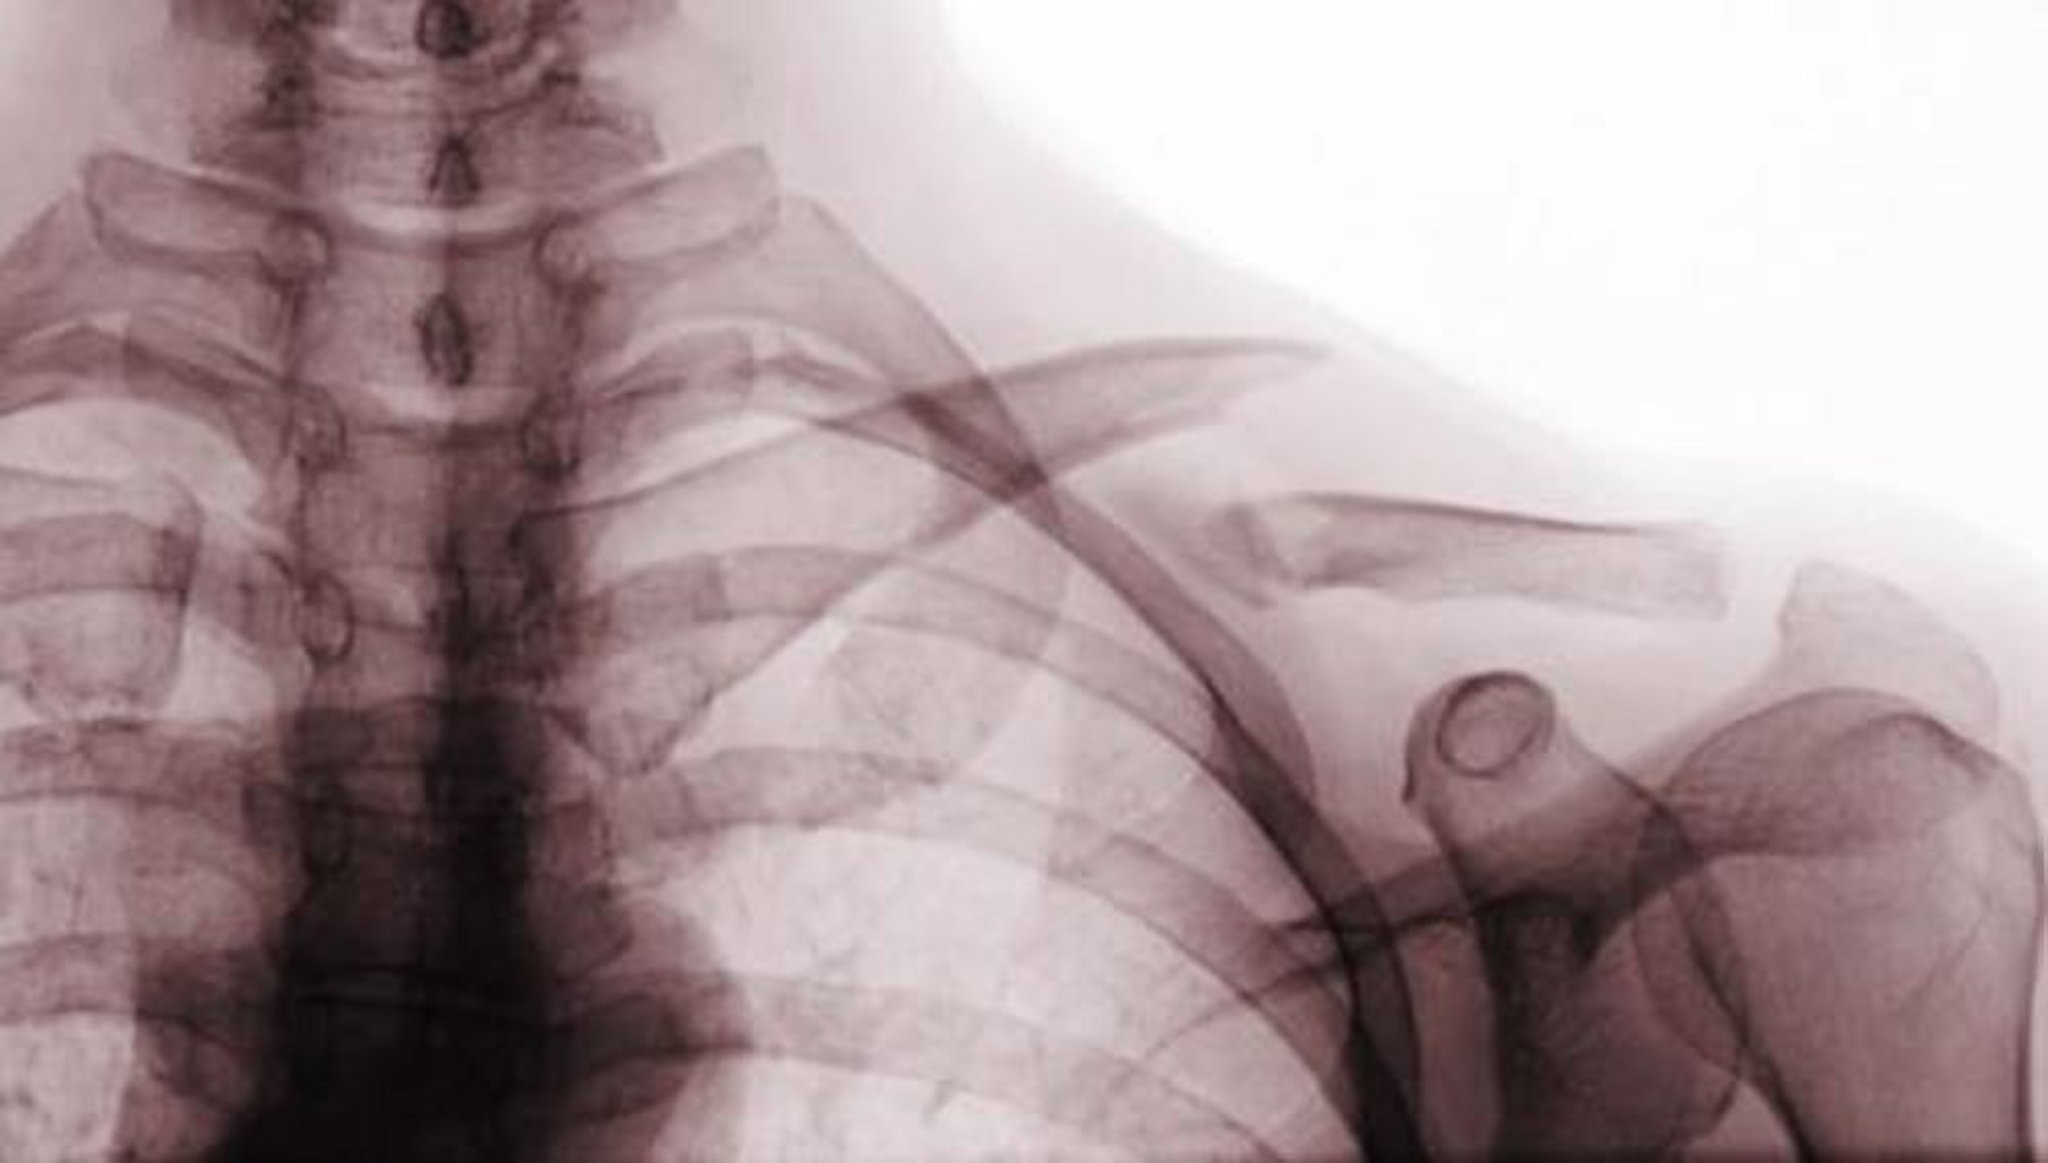

Questa vista radiografica antero-posteriore mostra una frattura spostata del terzo medio della clavicola (frattura di classe A).